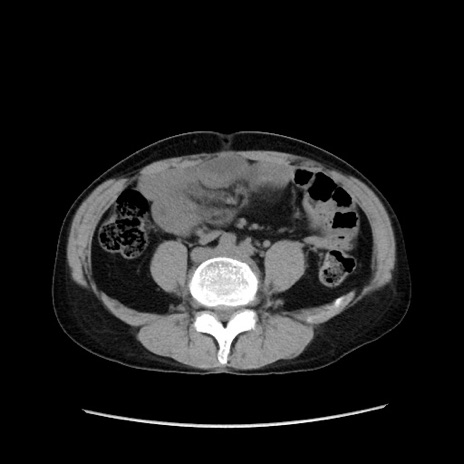

症例37(横断像)

【症例】40歳代 男性

【主訴】腹痛

【現病歴】4時間ほど前に電車に乗車中に臍部上より腹痛出現。徐々に増悪し起立困難となり、救急外来受診。生ものは数日食べていない。今朝お雑煮を食べた。

【身体所見】BT 36.8℃、BP 117/84mmHg、HR 91/min、SpO2 97%、苦悶様、腹部:臍上部広範囲圧痛あり、反跳痛±

【データ】WBC 8100、CRP 0.03